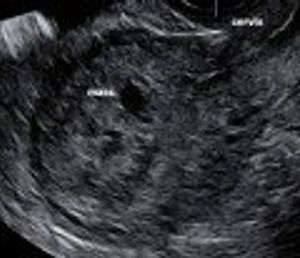

This case demonstrates the utility of 3D ultrasound, using the coronal plane as a reference point, for patients with an IUD who have pelvic pain.